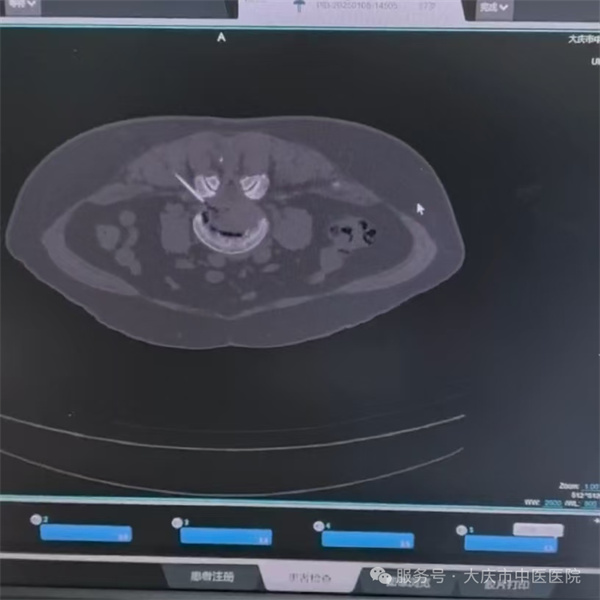

徐阿姨患有腰突症多年。近日,病情突然加重,腰背痛的同时伴有明显下肢麻木疼痛,行动大多要靠坐轮椅,很不方便,口服止痛药物也不能缓解症状,严重影响到日常生活。入院后,经骨科诊断明确,联系麻醉科、CT室会诊,第二天为徐阿姨在CT引导下行腰突症微创介入疗法。治疗后徐阿姨自述患侧腿感觉轻松许多,麻木疼痛感也缓解不少,随后步行返回病房。三日后,徐阿姨高高兴兴的办理了出院手续。

大庆市中医医院麻醉科副主任范晓刚介绍,腰突症微创介入疗法(LNIT)治疗机理:腰椎间盘在退变的基础上出现纤维环破裂,髓核的十几种化学物质被激活,释放到椎间盘后方的椎管内,刺激椎管内的脊神经,脊神经出现炎性肿胀、增粗、粘连,椎管内丰富的静脉丛也扩张、淤血。无论是口服还是静脉用药,能够进入椎管内的药物很少,同时,椎管内的炎症也被局限在椎管内,释放不出去,所以腰间盘突出患者的疼痛比其它软组织的损伤的疼痛更强烈。而CT引导下精准微创介入疗法,是在CT引导下通过椎间孔将药物精准地注射到纤维环破裂口的表面,受损伤的神经周围,起到消炎、止痛、活血、化瘀、营养神经、修复神经的作用,同时也起到冲洗和松解炎性神经根的作用,从而达到治疗目的。